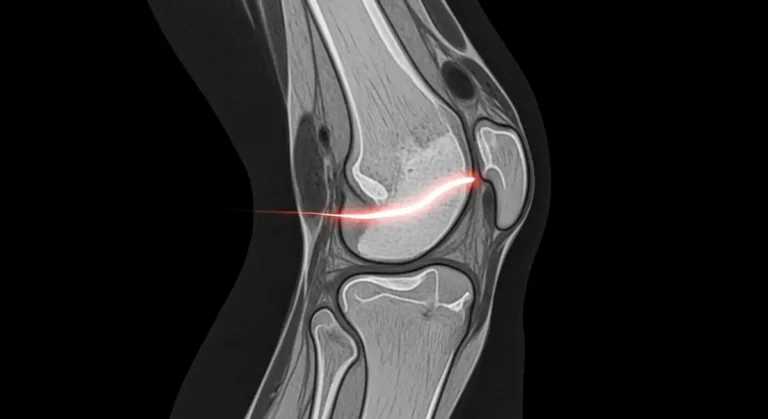

A síndrome de Osgood-Schlatter é uma dor irritativa no ponto em que o tendão patelar se ancora na tuberosidade da tíbia. Saltos, corridas e chutes aumentam a tração do quadríceps e inflamam essa área de crescimento. É comum em crianças…